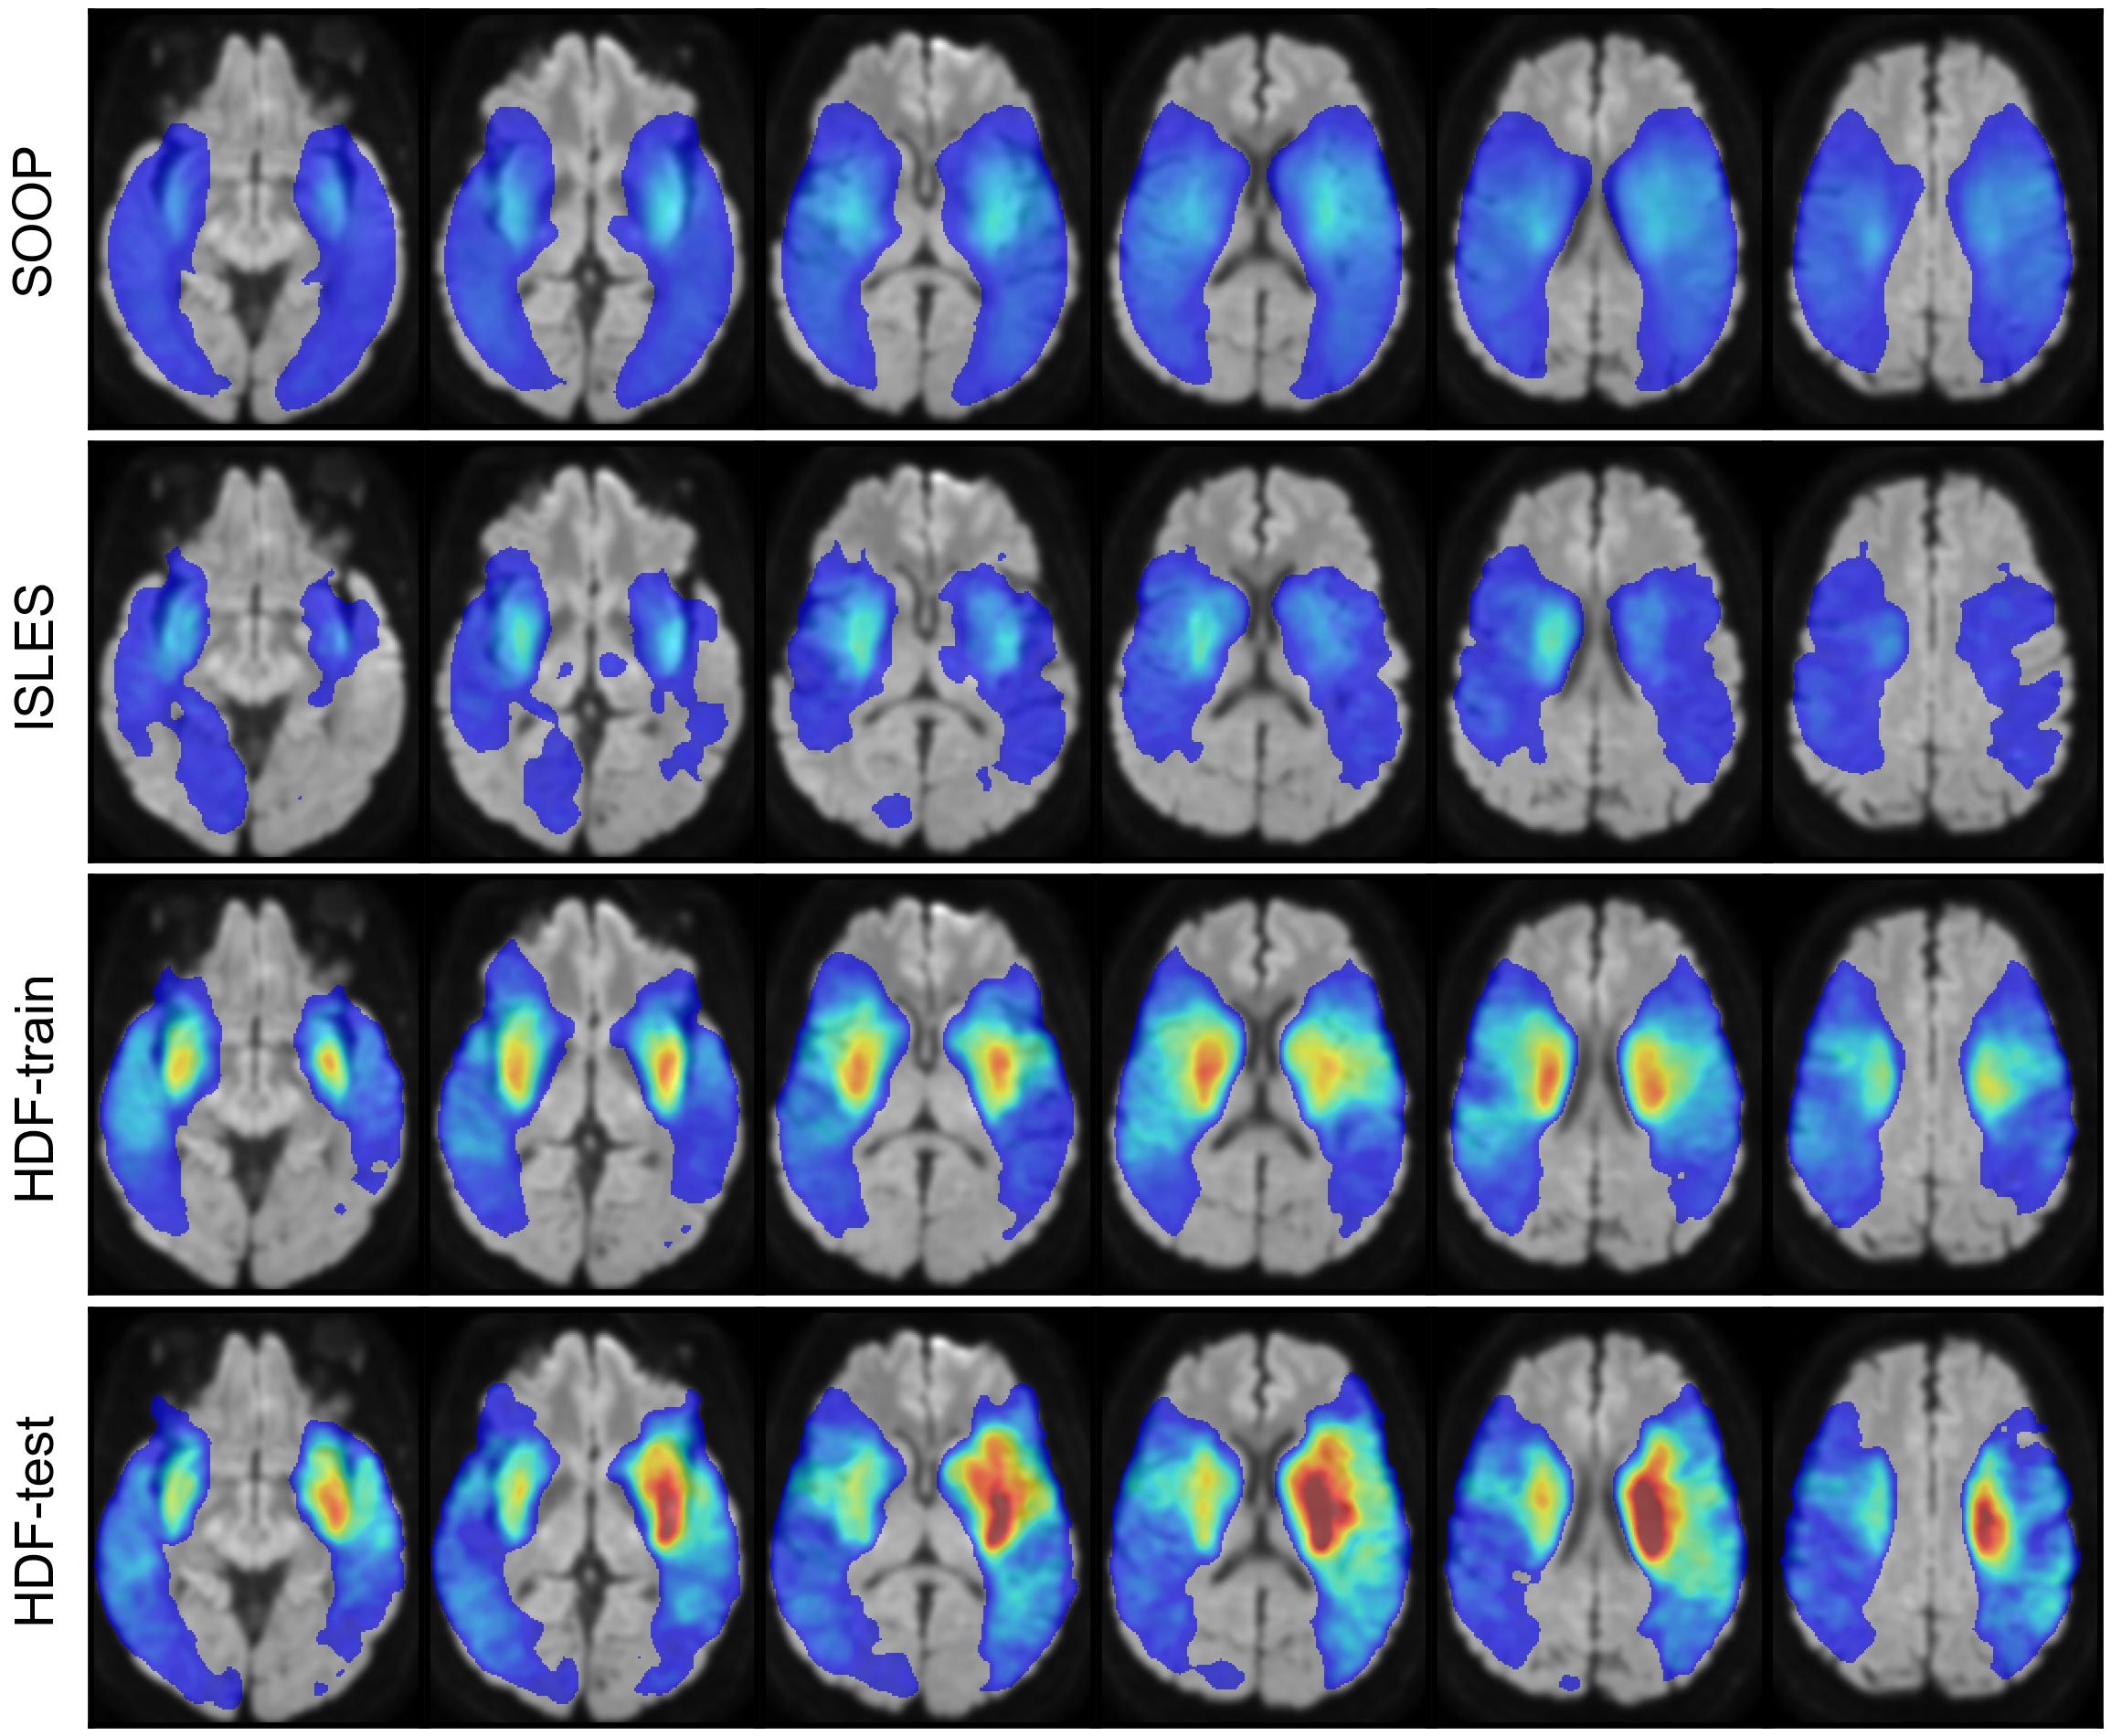

All datasets included stroke in similar regions, with a lower frequency for SOOP and ISLES (Figure 1).

The FP proportion map (Figure 5(a)) shows that both models exhibited a region of high FP concentration near the right corticospinal tract: slices 5 and 6 for ISLA-ENS, and slices 8 and 9 for DAGMNet. When examining the FN proportion map (Figure 5(b)) alongside it, it can be seen that the region of high FP concentration for ISLA-ENS coincided with lower FN proportions compared with DAGMNet (slices 5 and 6), whereas the converse was not true (slices 8 and 9). This suggests that ISLA-ENS’s tendency to be more sensitive to suspicious areas contributed to improved lesion detection, a pattern not observed for DAGMNet. In addition, ISLA-ENS produced fewer FPs in the superior posterior region of the brain (slices 5–9 in Figure 5(a)) and fewer FNs across a large inferior region (slices 1–7 in Figure 5(b)).

Figure 5(c) further shows that DAGMNet produced FPs that were, on average, farther from any true lesion compared with ISLA-ENS. For example, slices 5-9 exhibit elevated mean HDs in the posterior part of the brain for DAGMNet; most contributing cases displayed inhomogeneity artifacts (D). Slices 1-7 also show high mean HDs in the temporal region (particulary the left) for DAGMNet, likely caused by magnetic-susceptibility artifacts near the ears (D).

To a lesser extent, slices 8 and 9 of Figure 5(c) reveal two regions where both models displayed elevated mean HDs: one at the left posterior boundary and another in a small region along the right boundary. These high distances were attributable to a case with a severe inhomogeneity artifact in the former region and a case with a hematoma in the latter (D).

Regarding FN mean HD, although slightly higher values were observed in the right posterior superior region for ISLA-ENS—corresponding to regions where DAGMNet exhibited substantially higher FP mean HDs (Figure 5(c))—, no region showed comparably large average errors (Figure 5(d)).